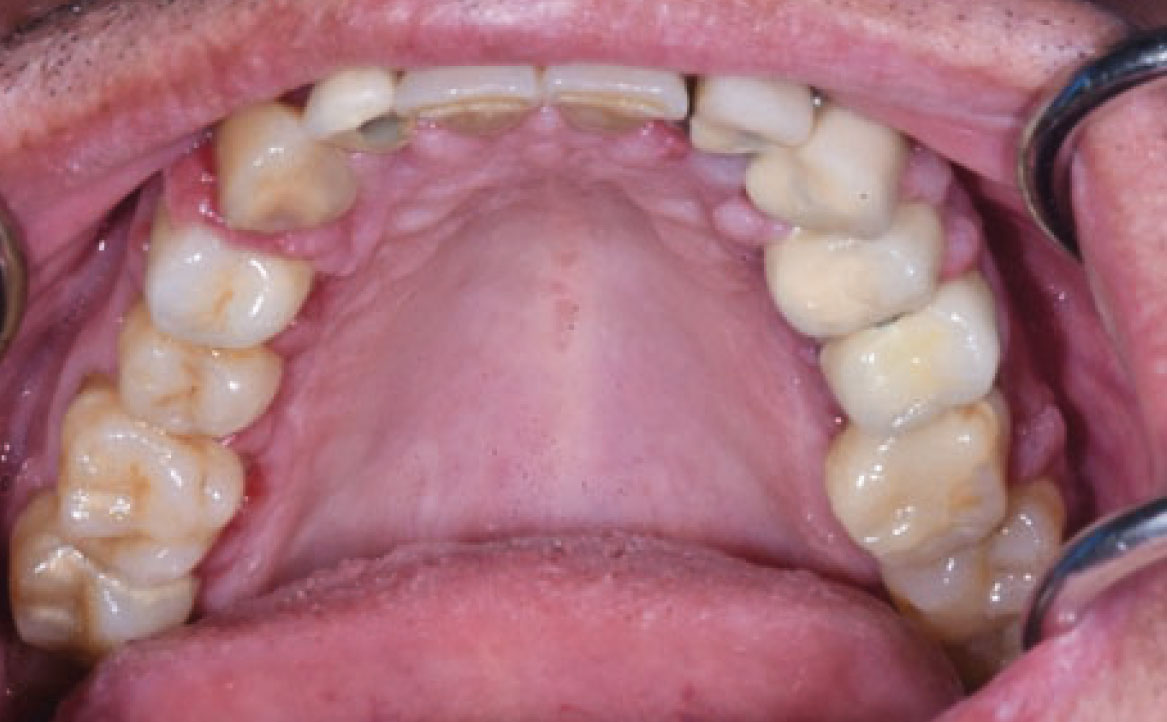

Il termine “aumento di volume gengivale farmaco-indotto” si riferisce comunemente a un effetto collaterale di alcuni farmaci utilizzati al di fuori della pratica odontoiatrica, per cui il tessuto gengivale non è il bersaglio previsto. Questi farmaci includono anticonvulsivanti come la fenitoina, che è la molecola più comunemente associata, immunosoppressori come la ciclosporina e calcio-antagonisti come la nifedipina (27) (fig. 10). Questa reazione avversa è principalmente legata a una predisposizione genetica e alla presenza di placca accompagnata da infiammazione gengivale, anche se i meccanismi esatti non sono ancora completamente compresi. La maggior parte dei farmaci responsabili agisce come inibitore dell’afflusso di ioni calcio. Questo porta a una diminuzione dell’assorbimento dell’acido folico nei fibroblasti del tessuto gengivale, il quale è essenziale per il corretto funzionamento della matrice delle metallo-proteinasi e l’attivazione delle collagenasi. Senza questa normale degradazione del collagene, si verifica un accumulo nel tessuto connettivale (28). Il trattamento può essere conservativo o chirurgico, mirando a ottenere un risultato estetico soddisfacente e a ridurre al minimo il disagio e il dolore. Se possibile, la sostituzione del farmaco implicato può portare alla regressione dell’iperplasia, supportata da un adeguato controllo della placca. Altrimenti, la soluzione chirurgica può essere l’unica opzione.

Clinicamente, i pazienti presentano un aumento di volume gengivale con pseudotasche, abbondante accumulo placca e difficoltà durante le manovre d’igiene orale domiciliare. Tale condizione è aggravata dall’infiammazione gengivale, conseguente all’accumulo di placca e tartaro, pertanto, è essenziale educare correttamente i pazienti sui potenziali effetti collaterali prima di iniziare qualsiasi trattamento farmacologico, sottolineando l’importanza di una igiene orale appropriata.